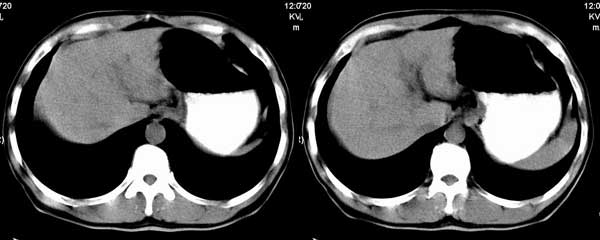

以下是引用听蝉观竹在2005-2-15 23:30:28的发言:[br]胃窦癌。[br]建议做胃镜检查并活检。